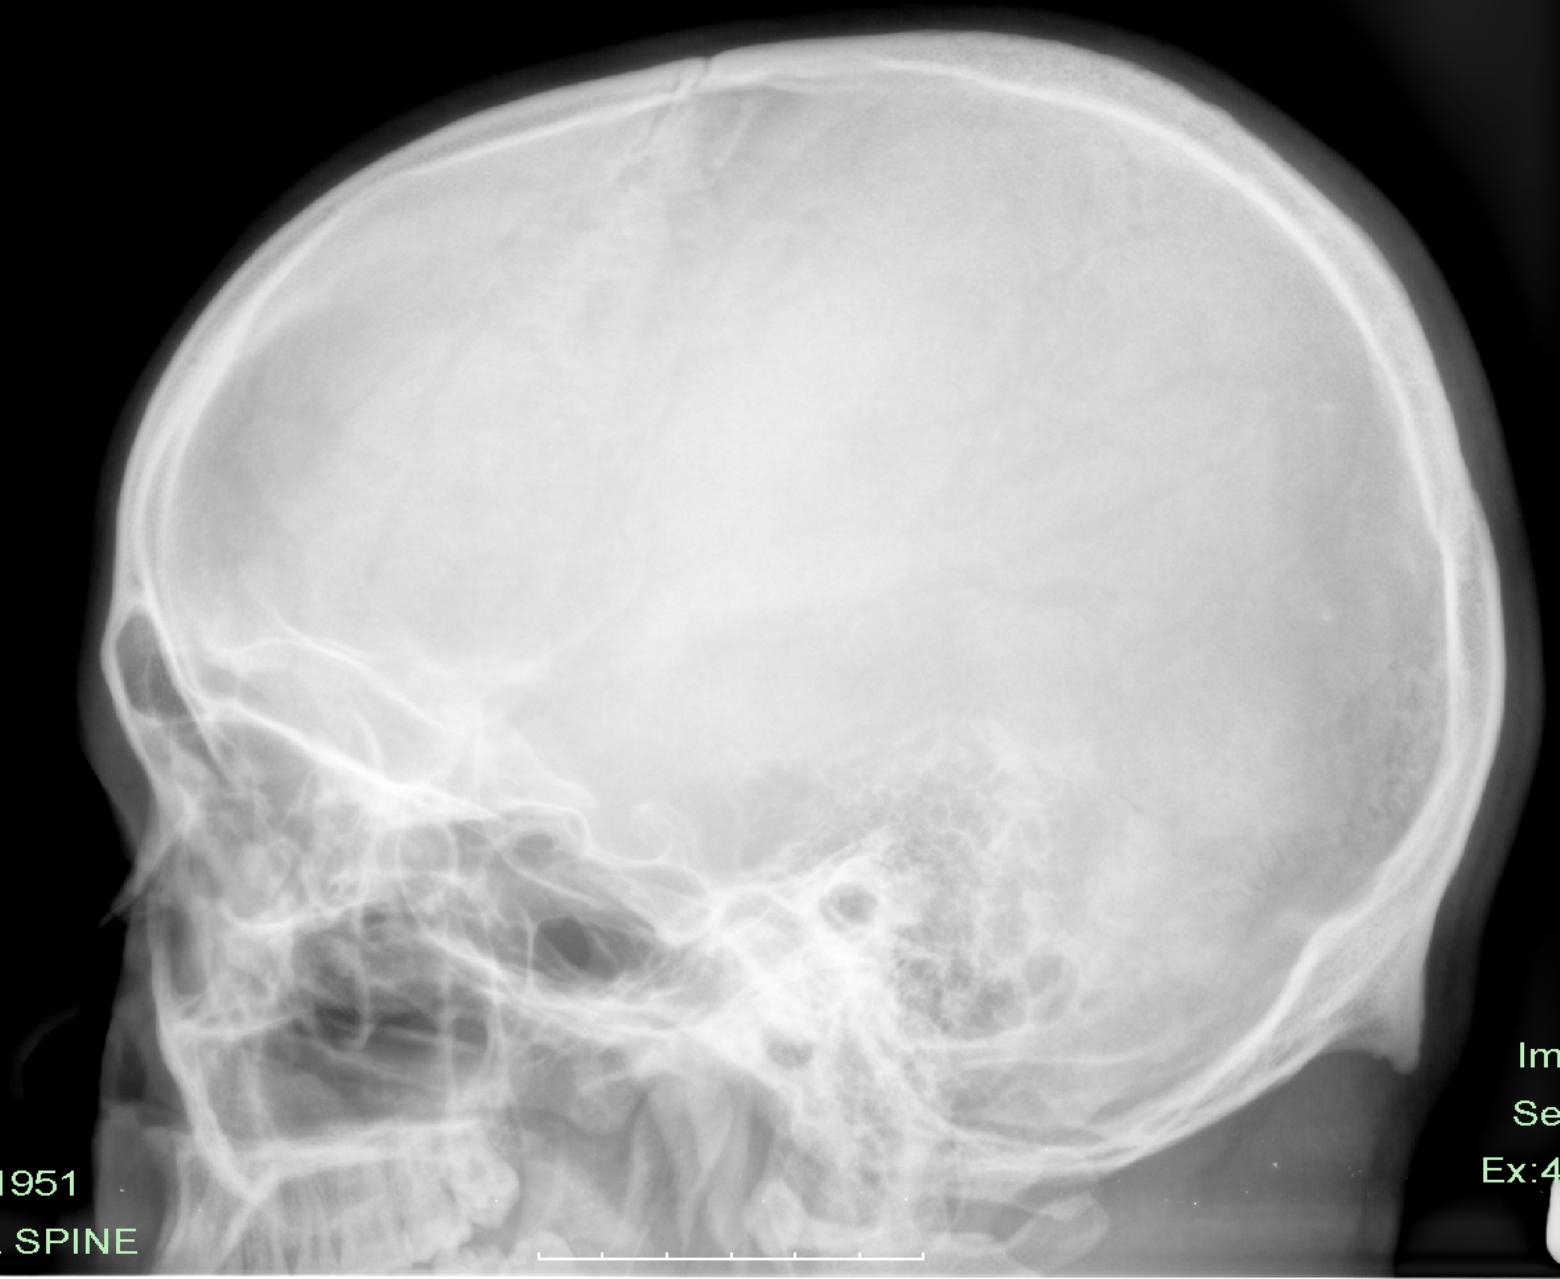

标题: X6458:发现后脑勺5年余。

补充:发现后脑勺硬物感5年余,不痛。

枕外隆突(正常变异)。

枕外隆突(古俗称反骨)。

枕外隆突(古俗称反骨)。有人就大些